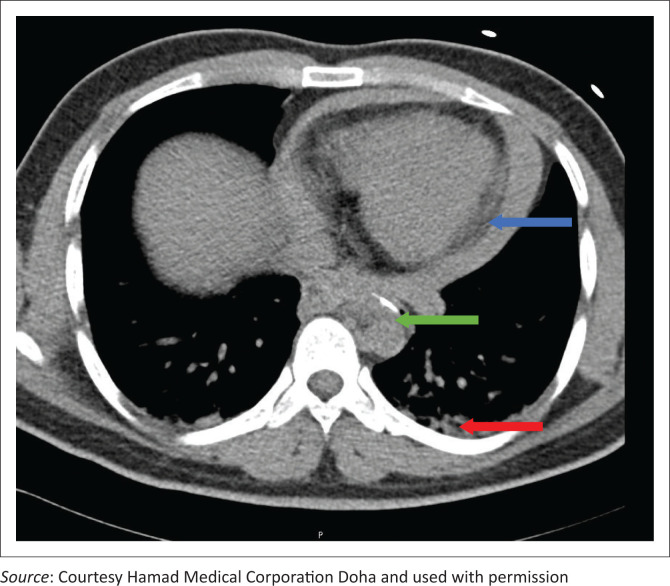

Background: Physicians often focus on possible cardiac causes in patients presenting with chest pain. However, this case highlights a patient who presented with chest pain caused by ingestion of a foreign body after an uneventful meal eaten an hour prior to presentation. The fishbone was discovered after imaging. The article aims to raise awareness regarding the potential origins of chest pain, highlighting that it may stem from non-cardiac conditions.

Results: The case report delineates the scenario of a 27-year-old male patient who inadvertently ingested a fishbone during a routine meal. It details the swift decline in clinical status, the meticulous diagnostic procedures employed, the subsequent management strategies implemented and the ultimate discharge of the patient in a stable condition.